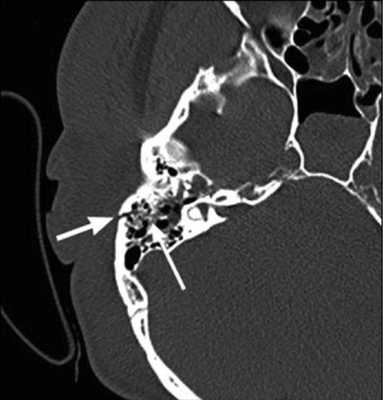

Невринома лицевого нерва в отличие от злокачественной опухоли характеризуется на КТ наличием в височной кости мягкотканного образования, имеющего достаточно ровные четкие контуры. Образование располагается по ходу одной из частей канала лицевого нерва и вызывает разрушение его костных стенок [5, 6, 9]. Невринома мастоидальной части лицевого нерва вследствие близкого расположения к наружному слуховому проходу часто распространяется в его просвет в виде округлого образования, вызывающего разрушение задней стенки (рис. 6). Рисунок 6. Невринома лицевого нерва. Аксиальная проекция левой височной кости. По ходу мастоидальной части канала лицевого нерва определяется объемное образование (1), распространяющееся в наружный слуховой проход (2). Стенки мастоидальной части канала лицевого нерва и задняя стенка наружного слухового прохода разрушены (стрелка). При клиническом осмотре в наружном слуховом проходе определяется образование плотноэластической консистенции на широком основании.